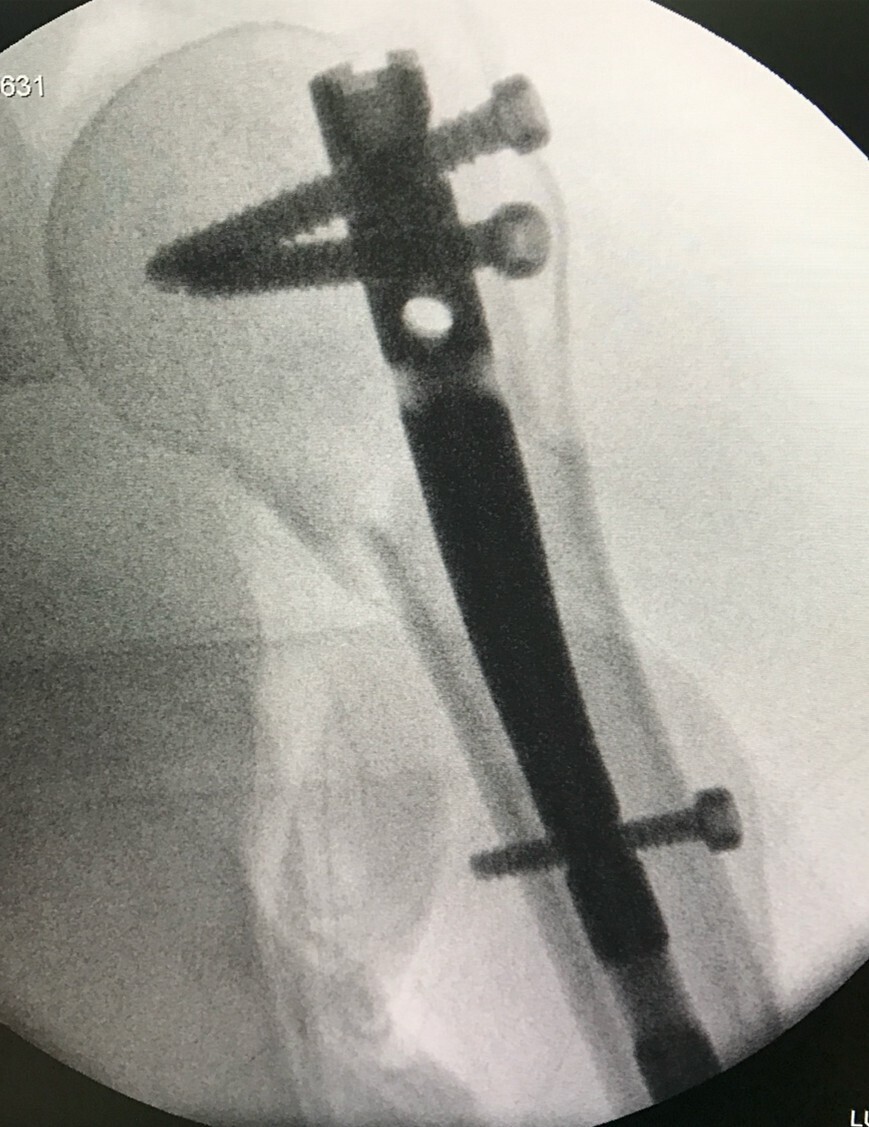

• l’ostéosynthèse consistant en une réduc­tion directe ou indirecte de la fracture, puis en son immobilisation par du matériel intra-osseux (broche, clous, vis, plaques), ou parfois à l’extérieur du membre (fixateur externe), notamment en cas de fracture ouverte grave (fig. 2). Une immobilisation complémentaire par attelle ou plâtre peut être associée.

L’évolution normale d’une fracture conduit à sa consolidation et au rétablissement de la fonction du membre. Cette évolution peut être compliquée par un déplacement secondaire, un retard de consolidation, une non-consoli­dation (pseudarthrose) ou une consolidation non anatomique (cal vicieux) [fig. 3], pouvant nécessiter des chirurgies complémentaires.